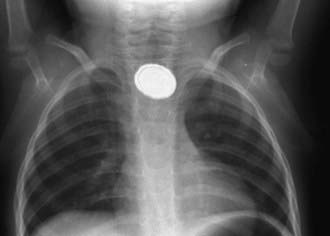

Evaluation of the child with a history of foreign body ingestion starts with plain anteroposterior (AP) radiographs of the neck, chest, and abdomen, along with lateral views of the neck and chest. The flat surface of a coin in the esophagus is seen on the AP view and the edge on the lateral view (Fig. 319-1). The reverse is true for coins lodged in the trachea; here, the edge is seen anteroposteriorly and the flat side is seen laterally. Disk batteries can look like coins (Fig. 319-2) and have a much higher risk of burns and necrosis (Fig. 319-3). Materials such as plastic, wood, glass, aluminum, and bones may be radiolucent; failure to visualize the object with plain films in a symptomatic patient warrants urgent endoscopy. Although barium contrast studies may be helpful in the occasional asymptomatic patient with negative plain films, their use is to be discouraged because of the potential of aspiration as well as making subsequent visualization and object removal more difficult.

image

Figure 319-1 Radiographs of a coin in the esophagus. When foreign bodies lodge in the esophagus, the flat surface of the object is seen in the anteroposterior view (A) and the edge is seen in the lateral view (B). The reverse is true for objects in the trachea.

(Courtesy of Beverley Newman, MD.)